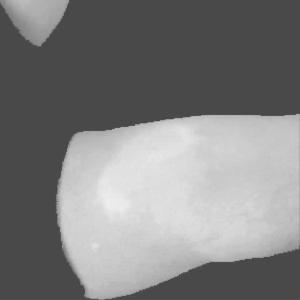

2.4.2 Laser Doppler Imaging dataset

The LDI dataset includes a 2D colour image and a scan that shows the severity of burns and their complementary healing potential (HP) using a color palette. This smaller dataset consists of a total of 184 skin burn images and their associated LDI scans. The images of this smaller dataset belong to three different burn depth/degree classes as follows; 114 SPT images, 49 DPT images, and 21 FT images. The LDI scans were captured using the moorLDI laser Doppler imager (Moor Instruments Ltd) which is a non-invasive imaging device.

In order for the LDI scans to be comparable with BAM binary segmentations, a number of processing steps were conducted. LDI scans can have different sizes, scales, and cropping in comparison to their corresponding burn images. As BAM uses the burn 2D colour images as the input for creating the binary burn segmentations, the LDI scans were first aligned with their corresponding burn images and converted into the same size as those images. Once the LDI scans are aligned with input images and their colors are processed in order to create binary masks, quantitative comparisons with BAM segmentations were conducted. For this purpose, we utilised the manual segmentations of burn areas from burn images validated by clinicians.

Moreover, as discussed later, it was discovered that the LDI scan color palette, which demonstrates different healing potentials, would classify uninjured areas and background noise in the image as burns with poor blood flow. In a clinical setting, this misclassification does not lead to a serious issue as scans are reviewed by clinicians who can easily differentiate between normal skin/background and burn area. However, since the processing of LDI scans is conducted by computer vision, this issue needed to be resolved. This was addressed by removing the non-burn areas from the LDI scans before processing LDI scans by multiplying the aligned LDI scans with the manual segmentations of burn areas resulting in LDI scans that show various healing potentials (or various degrees of burn) in the burn area only.